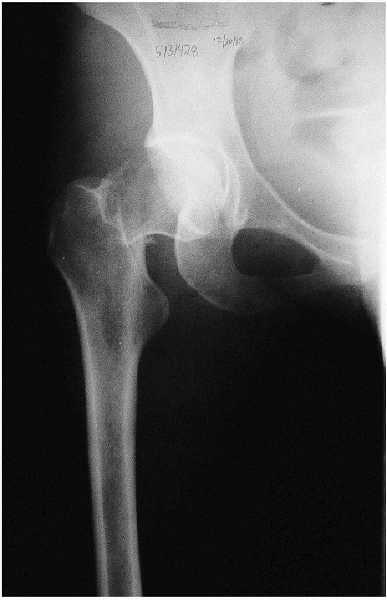

![]() |

FIGURE 21-5. Anteroposterior view of the pelvis.

Anteroposterior view of the pelvis (Fig. 21-5)

Anteroposterior and cross-table lateral view of the involved proximal femur (Figs. 21-6 and 21-7).

offsets the anteversion of the femoral neck and provides a true

anteroposterior view of the proximal femur. A second anteroposterior